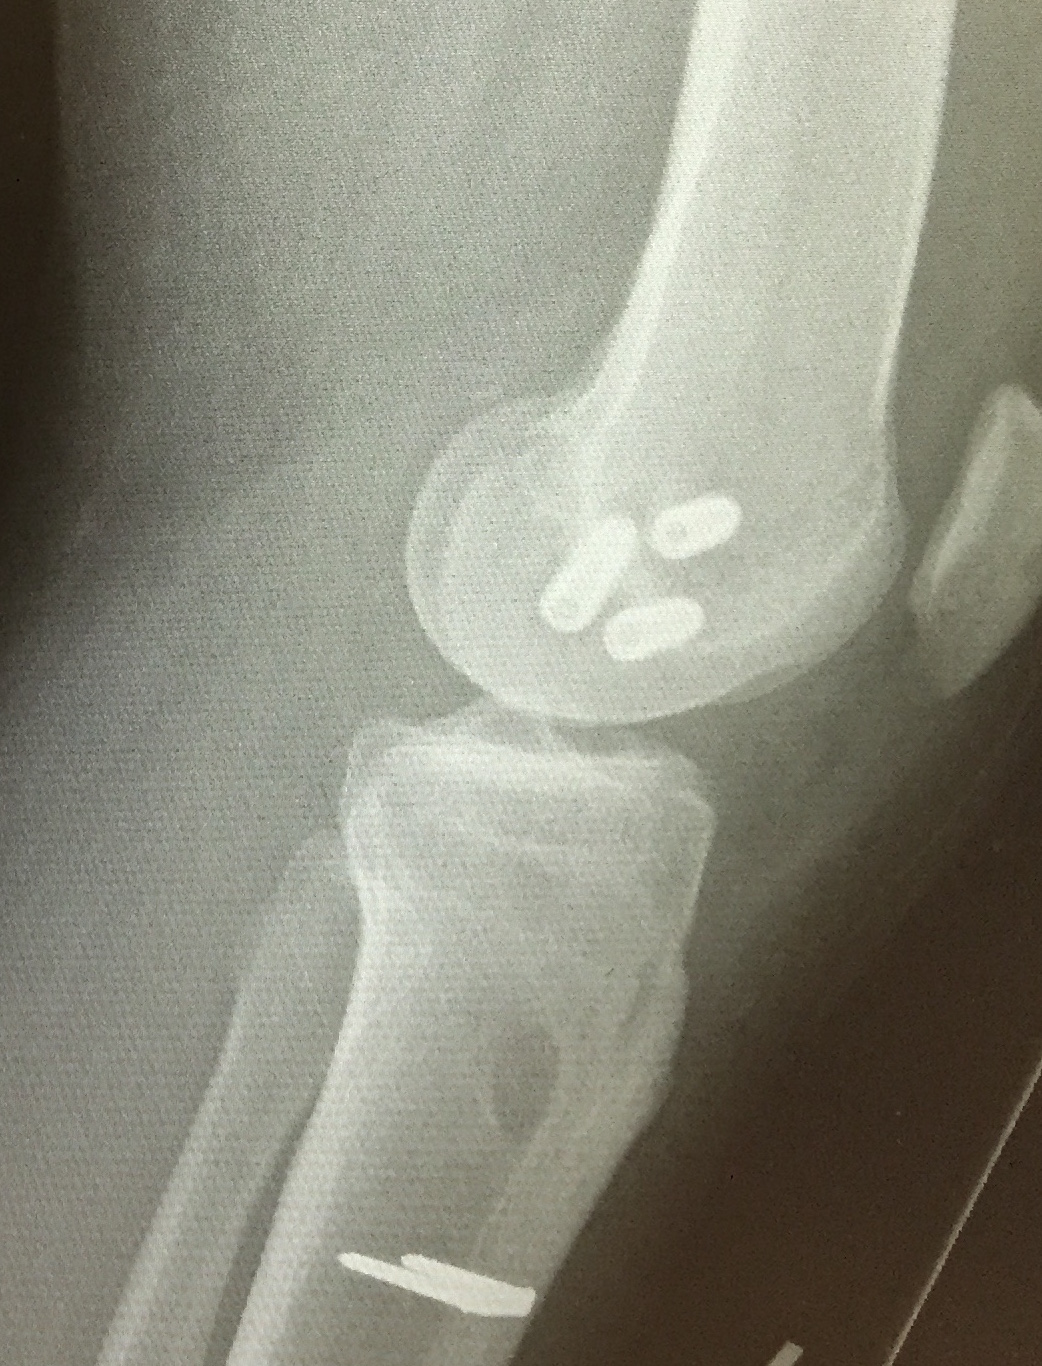

Right knee arthroscopy displaying empty medial femoral condyle. PCL jig has been placed and beath pin drilled outside in

PCL graft has been passed in right knee. ACL and PCL grafts passed

Xray following PCL reconstruction, LCL and politeus reconstruction. CT demonsrating popliteus and LCL tunnels